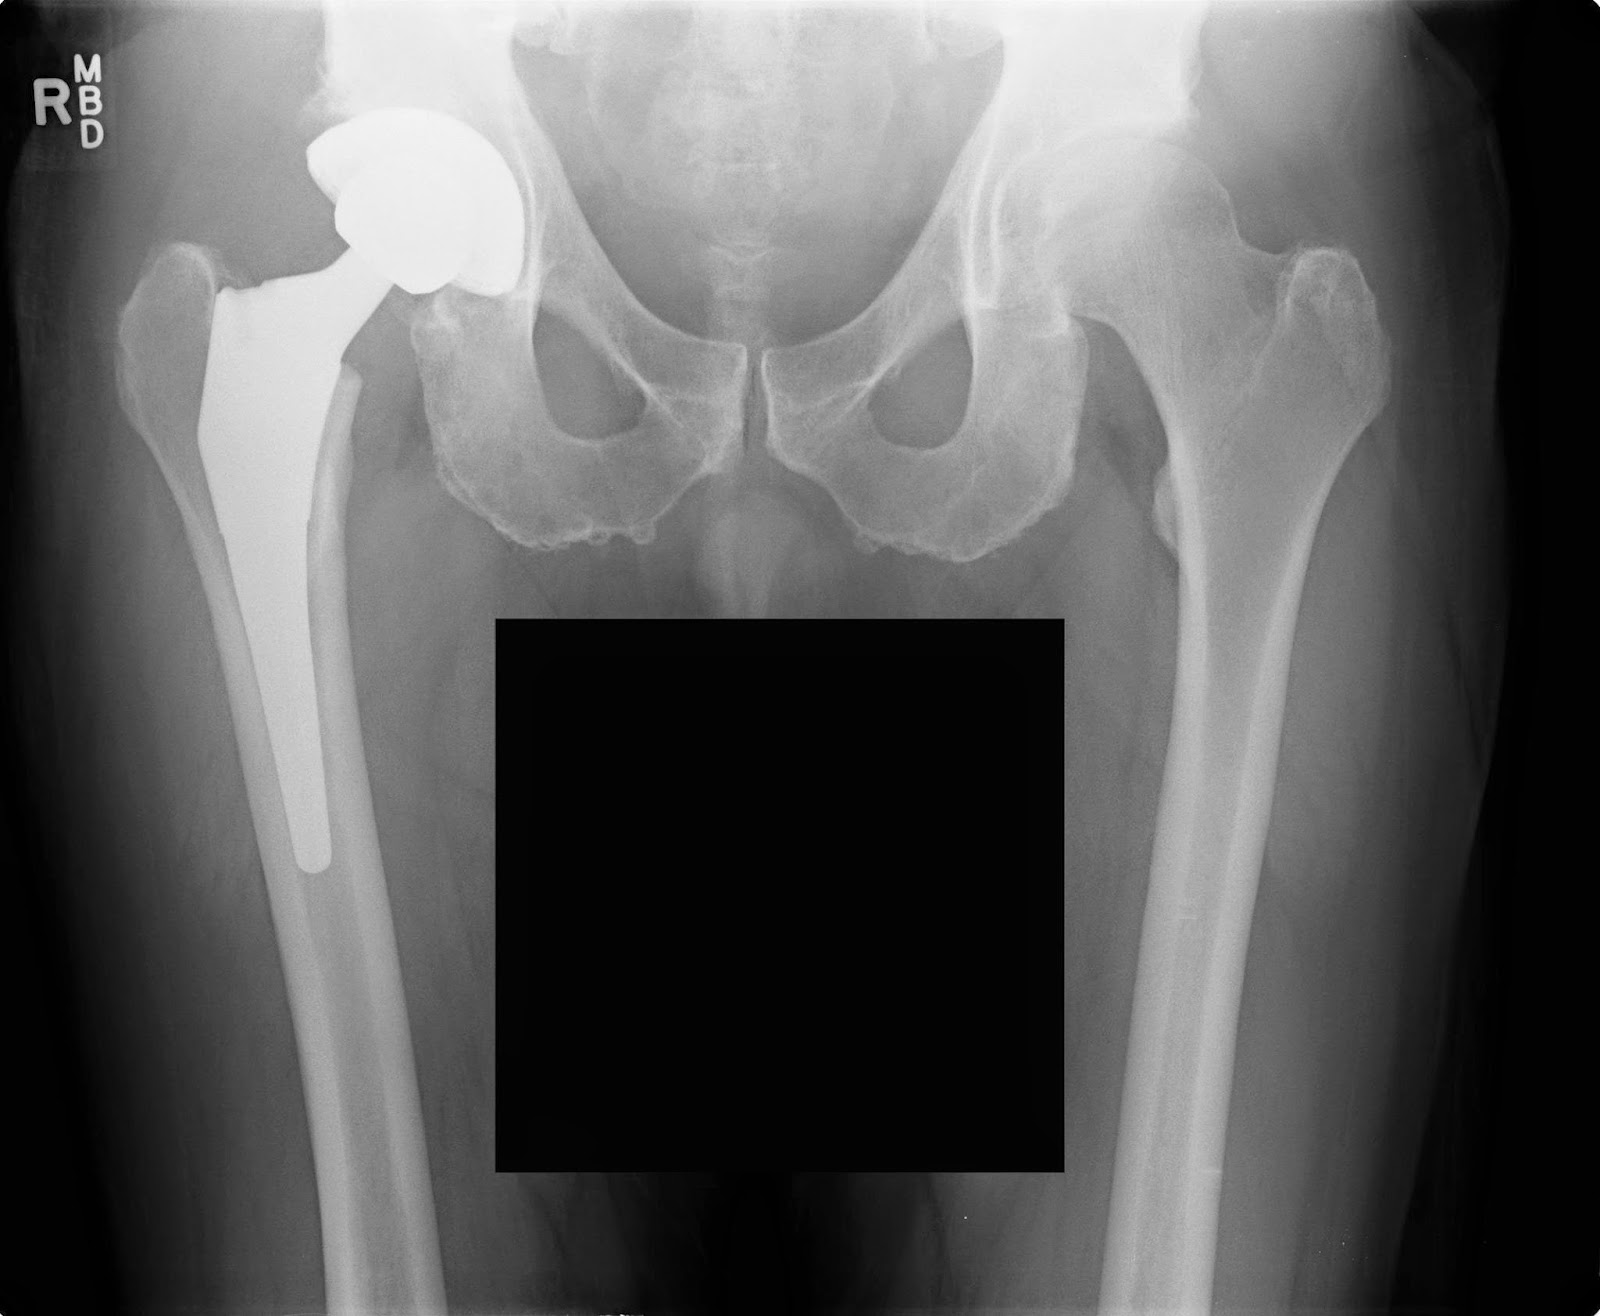

Hip Replacement Surgery How it Works, Recovery Time HSS